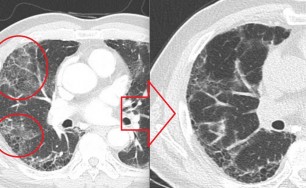

한약이 폐에서 항산화 작용을 하고, 염증관련 신호조절(항염증)을 한다는 연구논문입니다.

숨케어한의원에서는 전화예약을 받고 있습니다. 내원시 엑스레이, CT사진, 폐기능검사지를 가지고 오시면 자세한 상담이 가능합니다.